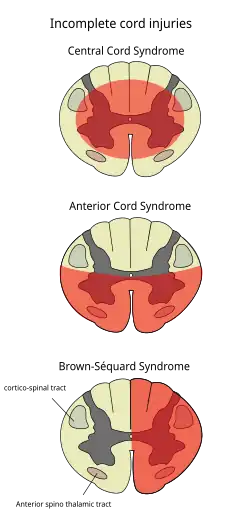

- Brown-Séquardův syndrom - hemisekce míchy vpravo nebo vlevo. Vzniká po penetrujících poraněních, při extramedulárních tumorech, RS, krvácení, ischemii, zánětu, či iatrogenně. Má relativně dobrou prognózu

- Komprese míchy zepředu - porucha motoriky, porucha čití pro bolest a teplo, zachované čití pro polohocit

- Intramedulární léze – hlavně v krční oblasti, porucha hybnosti výraznější na horních končetinách